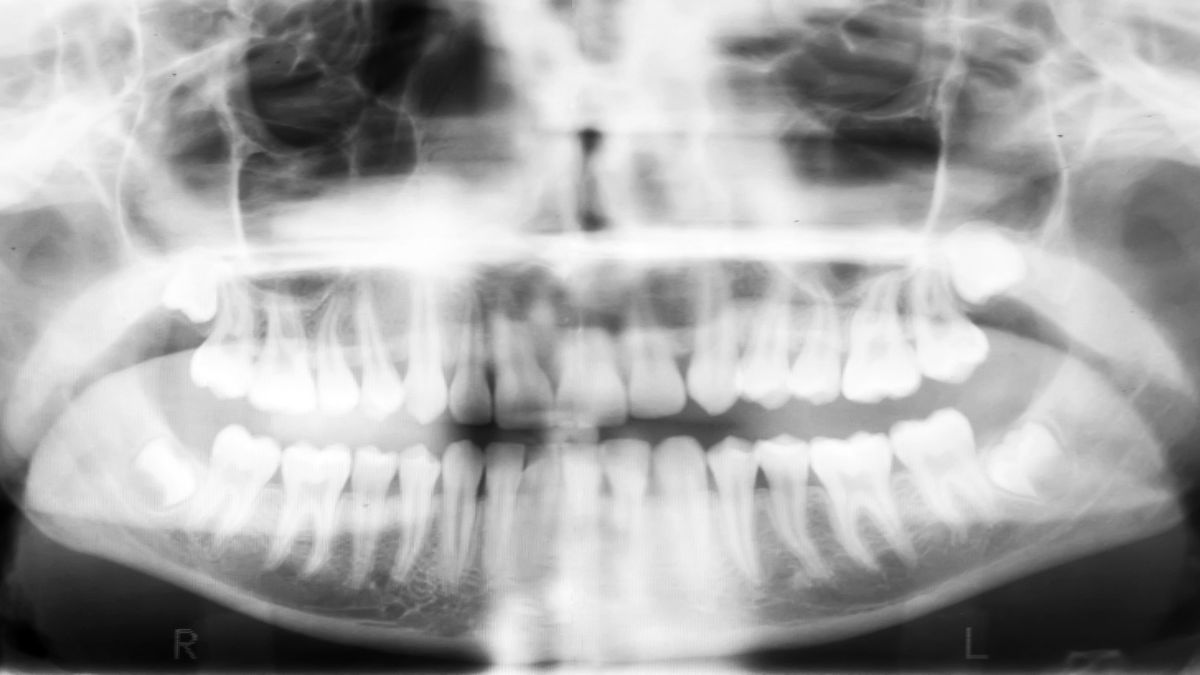

1. Panoramic X-ray Machine (Curved Tomography Machine): This device can capture panoramic images of the entire dentition, jawbone, and temporomandibular joint in a single shot, clearly displaying the arrangement of the entire dentition, jawbone morphology, and impacted wisdom teeth. It is a commonly used device for routine dental examinations.